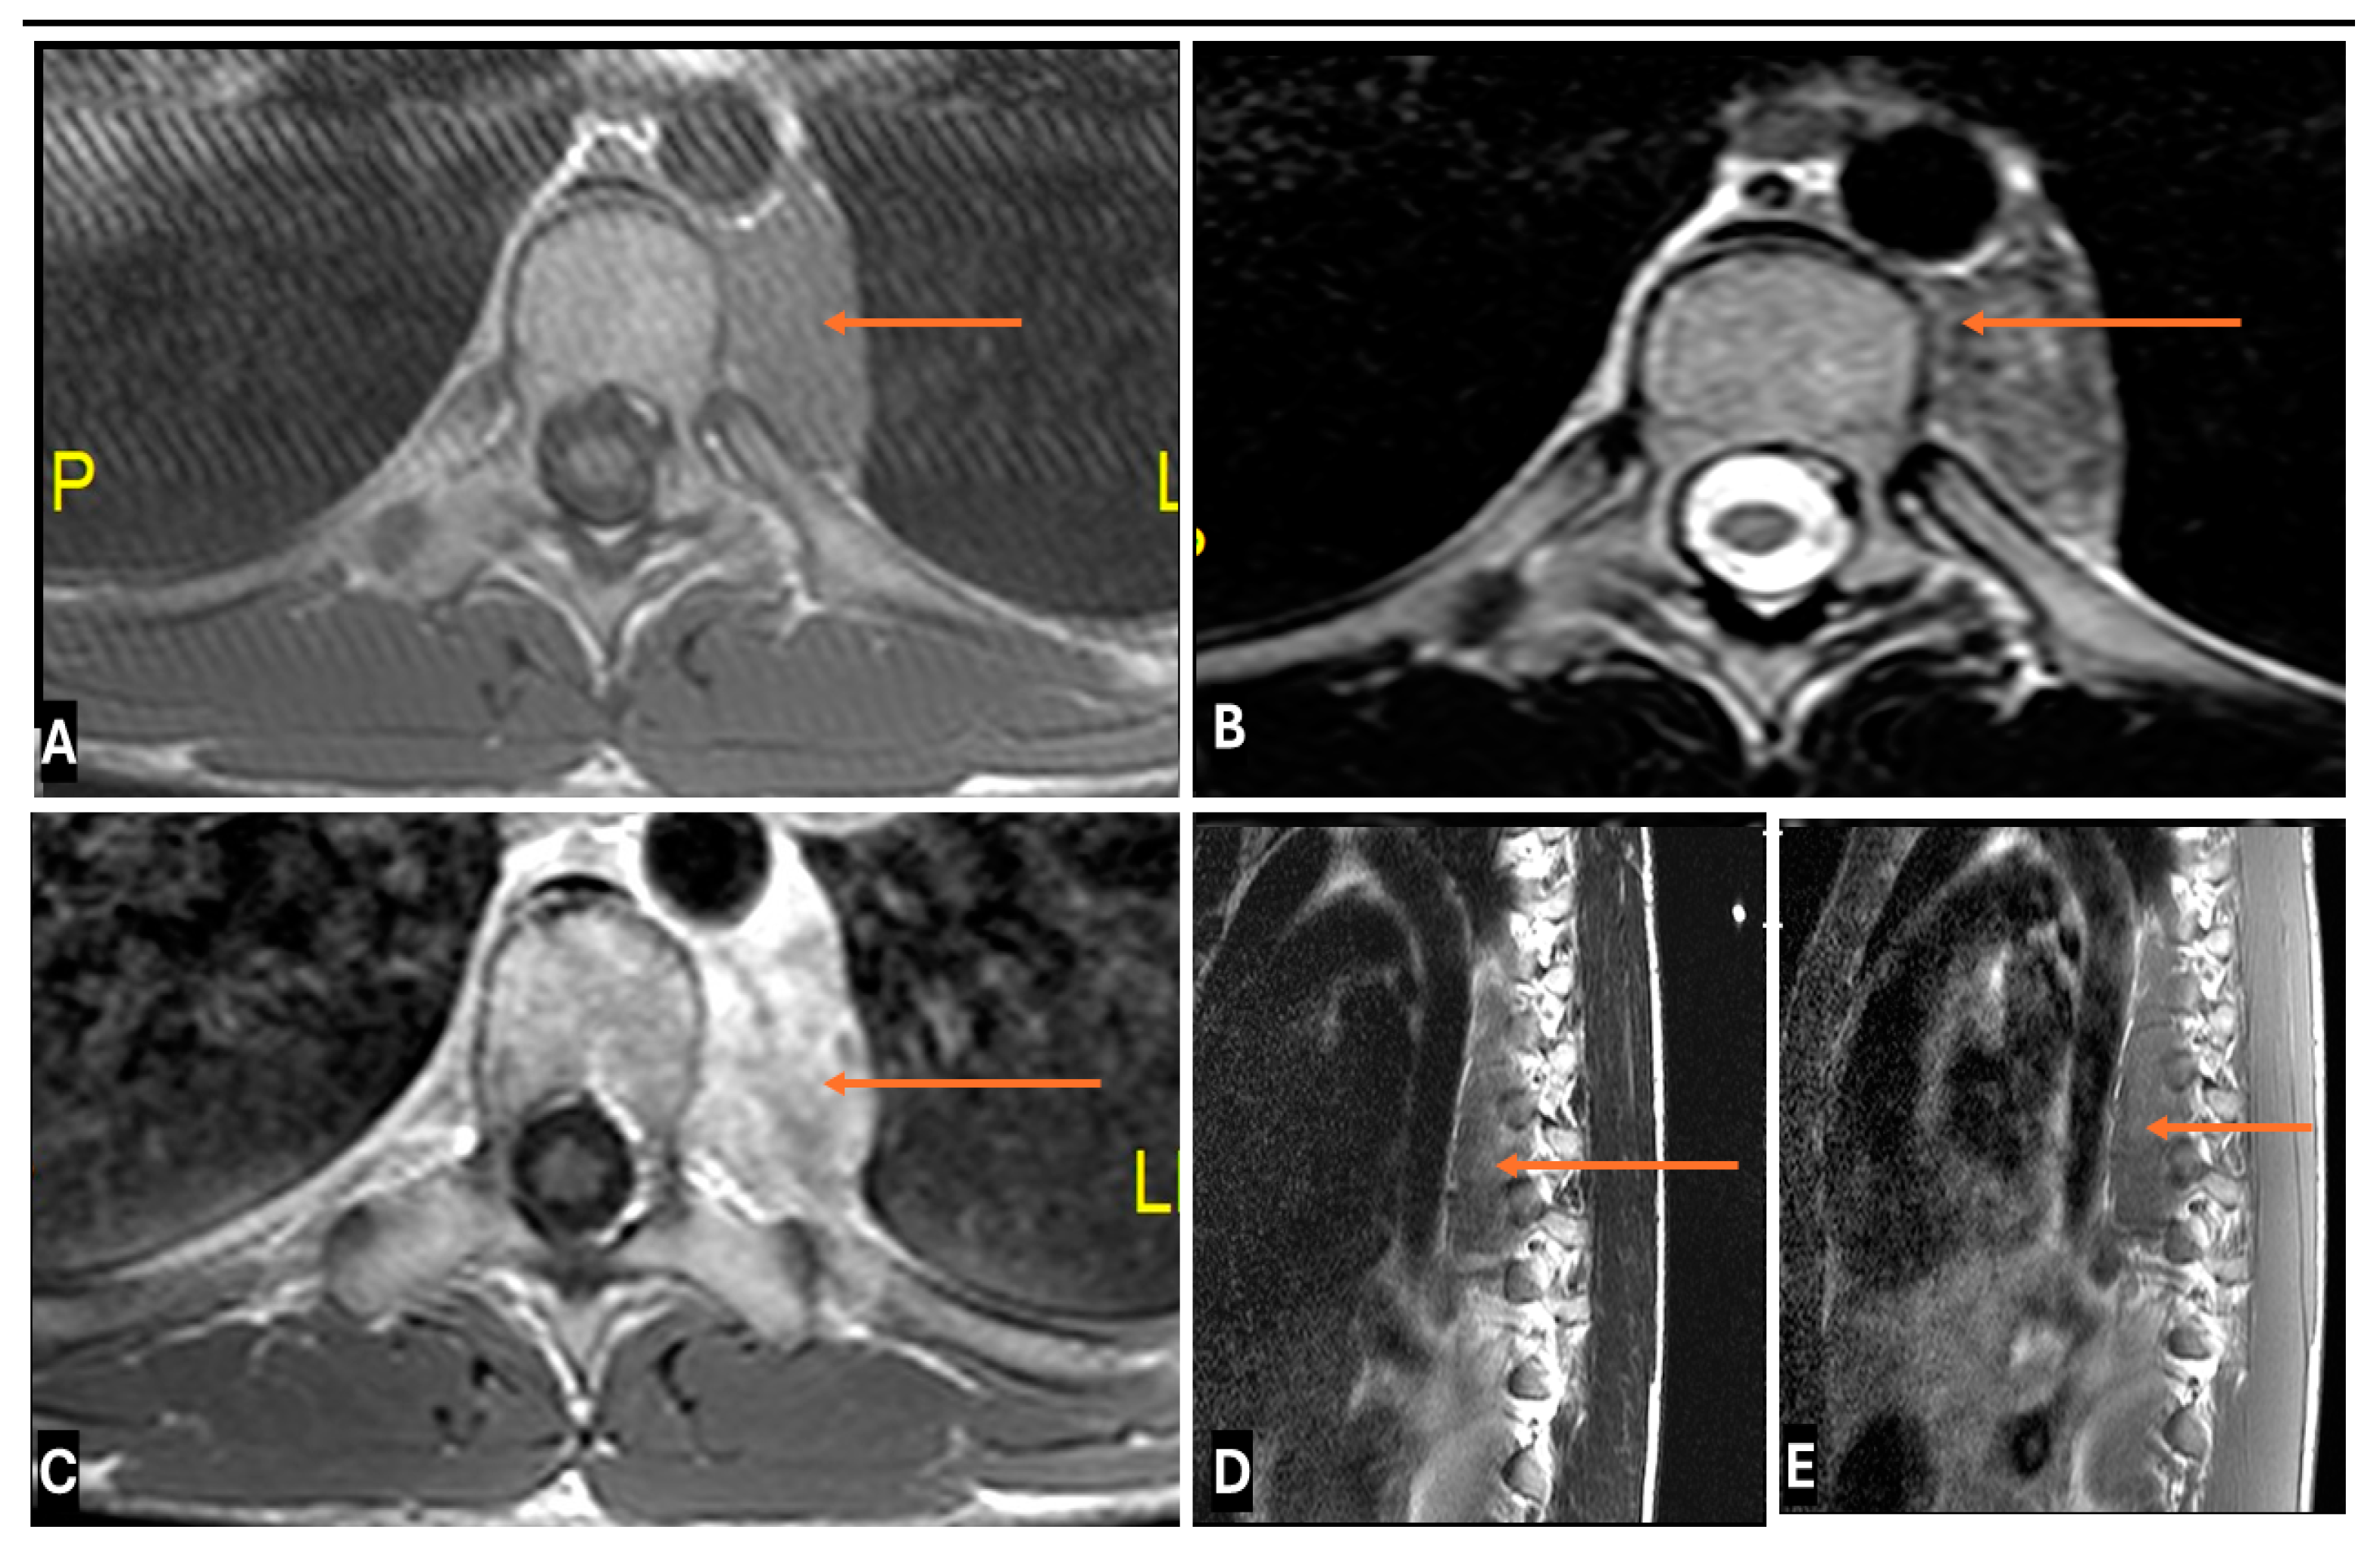

- Primary Sarcomas: Soft-tissue sarcomas are uncommon, accounting for just over 1% of adult malignancies. Synovial sarcoma, clear cell sarcoma, and epithelioid sarcomas are known to involve peripheral nerves. CT/MR reveals a large soft tissue mass with areas of necrosis or calcification and heterogeneous contrast enhancement. F-18 FDG uptake is useful for both tumor staging and treatment assessment (Figure 26, Figure 27 and Figure 28).